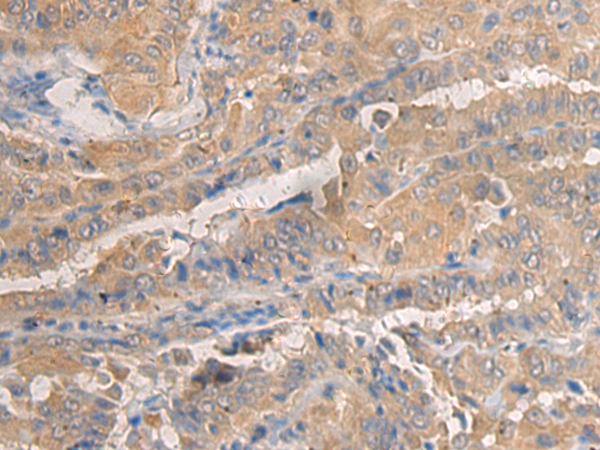

IHC positive control: |

Human thyroid cancer and Human breast cancer |

IHC Recommend dilution: |

50-100 |